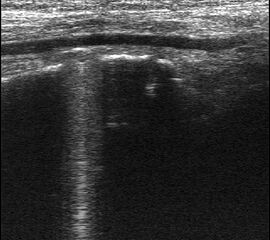

Ruptur Lig. fibulotalare anterius

Lagerung: Rückenlage, OSG in Plantarflexion.

Schnittebene: LS über Lig. talofibulare anterius.

Referenzstrukturen: Fibulakante und Talushals.

Befunde: Das Lig. talofibulare ant., verläuft (mit häufigen Anlagevarianten) beim Gesunden als meist dreieckige oder parallele echogene Struktur von der Fibula bis zur Spitze des im Schnitt pyramidenähnlichen Talus. Darunter ist ggf. Gelenkknorpel erkennbar (Abb. 15). Beim Erwachsenen reißt das Band meist distal ab und schlägt sich zum Talus hin ein (Abb. 16). Bei Kindern reißt das Band meist mit einer osteochondralen Schuppe fibular ab (Abb. 17). Zwischen Band und Knochen drängt oft echoarmes Hämatom nach außen, das im Dekompressionstest deutlicher darstellbar wird (Abb. 18). In derselben Untersuchungsposition kann die Stabilität schnell und weitgehend schmerzfrei überprüft werden (s. u.).